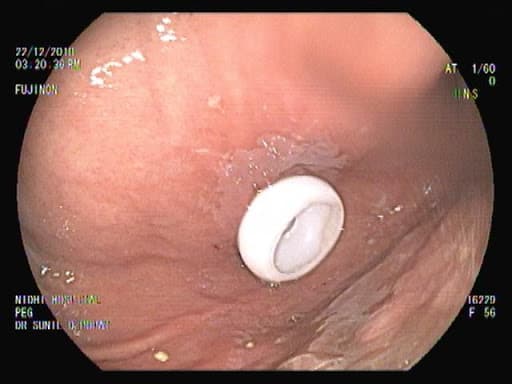

Percutaneous endoscopic gastrostomy, or PEG, is a procedure through which an endoscope assists the placement of a flexible feeding tube through the abdominal wall and into the stomach. The PEG procedure is for patients who have difficulty swallowing, problems with their appetite or an inability to take enough nutrition through the mouth. It allows nutrition, fluids, and/or medications to be put directly into the stomach, bypassing the mouth and esophagus.

In this procedure, the endoscopist uses a lighted, flexible tube called an endoscope to guide the creation of a small opening through the skin of the abdomen and directly into the stomach. This allows the doctor to place and secure a feeding tube into the stomach. Patients generally receive a mild sedative and local anesthesia, and an antibiotic is given by vein prior to the procedure. Patients can usually go home the day of the procedure or the next day.

A PEG does not prevent a patient from eating or drinking, but depending on the medical condition and situation, the doctor might decide to limit or completely avoid eating or drinking.

PEG tubes can last for months or years. However, because they can break down or become clogged over extended periods of time, they might need to be replaced. The doctor can remove or replace a tube without sedatives or anesthesia, although he or she might opt to use sedation and endoscopy in some cases. PEG sites close quickly once the tube is removed, so accidental dislodgment requires immediate attention.